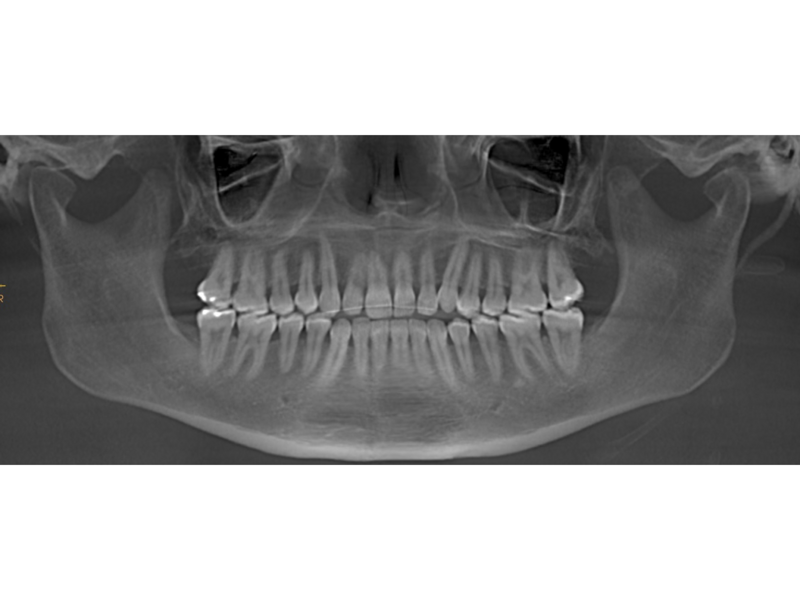

A 30-year-old female patient presented with the chief complaints of severe muscle and joint pain, open bite and tooth wear. She was treated orthodontically as a teenager with fixed appliances. Extra-orally, we observed slight mandibular asymmetry with deviation of the chin to the right, as well as lip incompetence, insufficient chin projection and a long face typical of a dolichofacial skeletal pattern (Fig. 2). Intra-orally, she had an anterior open bite, retroclined maxillary incisors, moderate crowding in both arches, an asymmetrical arch form uneven gingival margins, a mandibular midline shifted to the right, abfractions, gingival recession and wear facets (Fig. 3). The joint and muscle examination revealed pain on palpation of the masseter, temporalis, and superior right and left lateral pterygoid muscles. She also exhibited pain in the bilaminar zone and both lateral poles of the condyles. Clinically, she had early clicking during mandibular opening and closing owing to anterior displacement of the articular disc in both joints. In the dental panoramic tomogram, she was missing all four third molars, but had no other noteworthy pathology (Fig. 4). Cephalometrically, she had a dolichofacial skeletal pattern and proclination of the mandibular incisors (Fig. 5).

We performed a visual treatment objective, and our goals were to lingualise the mandibular incisors, decrease the vertical dimension through intrusion of the posterior teeth and produce anticlockwise rotation of the mandibular plane. This would improve the patient’s facial profile, lip competence and articular function. The CBCT images of the joints showed that both condyles were improperly located within the fossae (Fig. 6). The joint spaces were increased and the condyles descended. The airway area on the CBCT scan showed compression (Fig. 7). The patient was referred for a polysomnographic study to rule out compromised respiratory function.